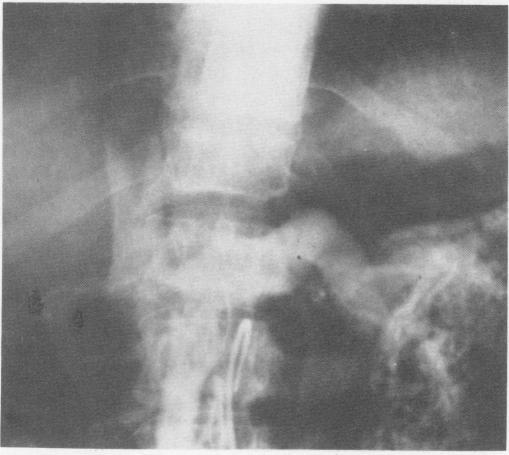

Controversy still surrounds the place of portalsystemic shunting in the therapy of bleeding esophageal varices. Recently, a selective shunt, the distal splenorenal shunt, has achieved some degree of popularity and, apparently, is associated with less chronic encephalopathy. Because of this, a trial was initiated at the Massachusetts General Hospital and continued at the University of Cincinnati Medical Center, prospectively randomizing central and distal splenorenal shunts in consecutive elective cases of patients with established variceal bleeding. Preoperative evaluation included endoscopic examination at the time of hemorrhage, angiography and upper gastrointestinal series, emphasis on mental function including EEG, amino acids, neurologic examination, as well as standard liver chemistries. Nineteen patients underwent central splenorenal shunts and 23 distal splenorenal shunt. There was one operative death from hemorrhagic pancreatitis in a Child's Class A patient with distal splenorenal shunt. Four late deaths, from gunshot wound, auto accident, overwhelming pneumonitis similar to postsplenectomy syndrome, and metastatic carcinoma (2.5 years after operation), have been recorded in the distal splenorenal shunt group, and none in the central splenorenal shunt group. On follow-up angiographic examination, six shunts have clotted, with three patients requiring reoperation, generally mesocaval shunt. There has been no chronic encephalopathy, three individual episodes of encephalopathy, two in the central splenorenal shunt group and one in the distal splenorenal shunt group, two associated with gastrointestinal bleeding and one with intercurrent infection and overdiuresis. Follow-up liver chemistries and amino acids which may be useful as an indicator of hepatic function suggest that although the distal shunt group had a better amino acid pattern before operation, branched-chain amino acids tend to become lower in the distal group while remaining the same in the central group. Aromatic amino acids increase post shunt, equally in the two groups. The results do not support the contention that distal splenorenal shunt is associated either with greater survival or freedom from encephalopathy than central splenorenal shunt, a small side-to-side shunt. Ascites seems better controlled by the central splenorenal shunt.

门体分流术在食管静脉曲张破裂出血治疗中的地位仍存在争议。最近,一种选择性分流术,即远端脾肾分流术,已受到一定程度的欢迎,而且显然与较少的慢性脑病相关。因此,马萨诸塞州总医院开展了一项试验,并在辛辛那提大学医学中心继续进行,对连续择期的确诊静脉曲张破裂出血患者前瞻性随机分配行近端和远端脾肾分流术。术前评估包括出血时的内镜检查、血管造影和上消化道造影,重点是精神功能,包括脑电图、氨基酸、神经学检查以及标准的肝功能检查。19例患者接受了近端脾肾分流术,23例接受了远端脾肾分流术。1例接受远端脾肾分流术的儿童A级患者死于出血性胰腺炎。远端脾肾分流术组记录到4例晚期死亡,分别死于枪伤、车祸、类似于脾切除术后综合征的严重肺炎和转移性癌(术后2.5年),近端脾肾分流术组无晚期死亡病例。在随访血管造影检查中,6个分流道发生血栓形成,3例患者需要再次手术,通常是行肠系膜上腔静脉分流术。未出现慢性脑病,有3次个体性脑病发作,2例在近端脾肾分流术组,1例在远端脾肾分流术组,2例与胃肠道出血有关,1例与并发感染和过度利尿有关。作为肝功能指标的随访肝功能检查和氨基酸检查结果表明,尽管远端分流术组术前氨基酸模式较好,但远端组支链氨基酸趋于降低,而近端组保持不变。分流术后芳香族氨基酸均升高,两组相同。结果不支持以下观点,即远端脾肾分流术比近端脾肾分流术(一种小型侧侧分流术)具有更高的生存率或更低的脑病发生率。近端脾肾分流术似乎能更好地控制腹水。